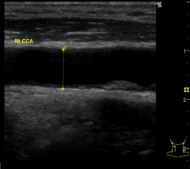

脳ドックで評価できるのは、無症候性脳梗塞(かくれ脳梗塞)、未破裂脳動脈瘤、脳腫瘍、そして認知症です。MRIやエコーに加えて、血液検査、心電図、神経学的診察では、動脈硬化や脳卒中を起こしうる不整脈(心房細動)、パーキンソン病や本態性振戦の有無が評価できます。

頸動脈エコー検査

頸動脈エコー検査(エコー検査は省略可です)